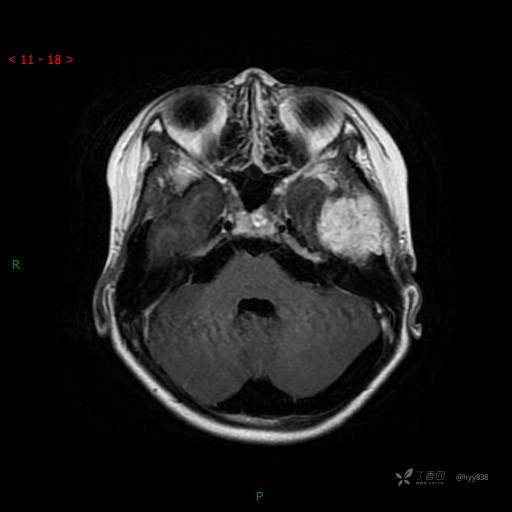

“典藏”病例分享。10岁儿童,头痛头晕一周余,CT、MRI 都有---结果公布~

简要病史:患者于一周前无明显诱因开始出现头痛头晕,无恶心呕吐,无肢体抽搐,无寒颤高热,无腹胀腹泻,无视力下降及视野缺损,上述症状休息后可稍缓解,未引起重视。 2天前患者头痛头晕不适加重,伴有恶心感,无呕吐,遂到当地人民医院行头颅CT检查示:左侧颞部占位性病变,今日家属为求进一步治疗,来我院门诊求治。门诊拟“左侧颞部占位性病变”收入我科。 患病以来,患者精神、饮食、睡眠尚欠佳,大小便如常,体力体重无明显变化。

临床诊断:左侧颞部占位

颅脑CT扫描